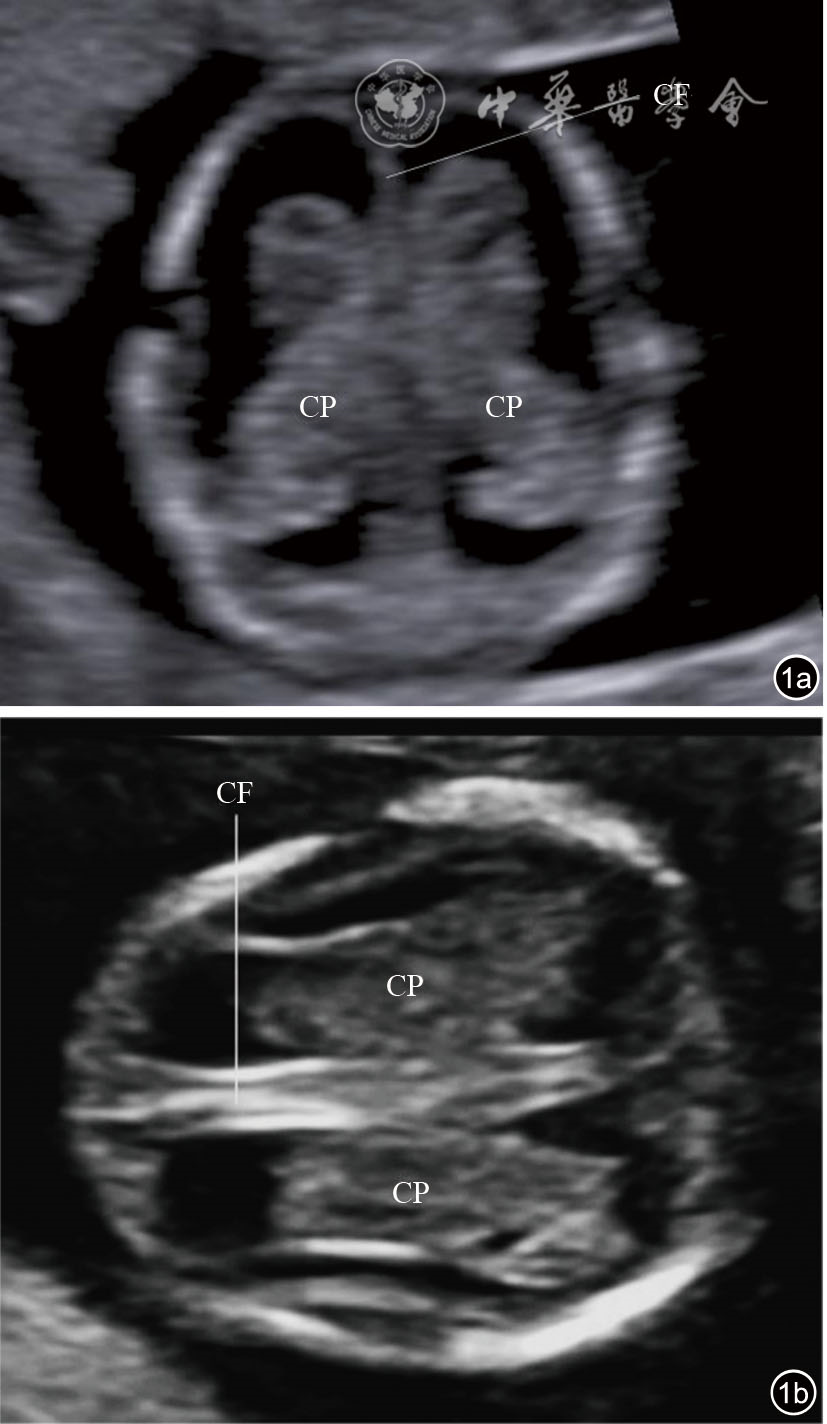

图1 妊娠早期经侧脑室横切面超声图像。图a为妊娠12+4周胎儿经前额侧脑室横切面声像图;图b为妊娠13+3周胎儿经颞部侧脑室横切面声像图 注:CP为脉络丛;CF为大脑镰